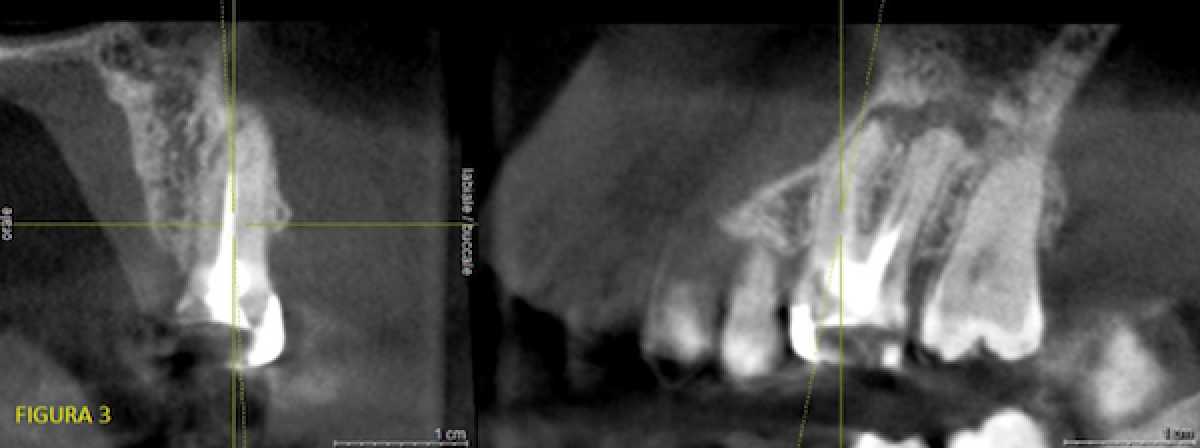

After observing the CBCT performed 4 years earlier at a resolution of about 100 microns, we were able to state that the apical radio-transparency, while present, was smaller and that, unfortunately, it was impossible to obtain endodontic morphology information useful for facilitating treatment (Fig. 3).

Stating first that I am a general dentist, and that an endodontic specialist with an expert eye would probably have been able to respond on the basis of a simple X-ray and perhaps also proceed successfully with therapy without further tests, we decided on a 'best quality' 4x4 CBCT (high resolution) to investigate the case further.

This examination revealed the presence and patency of a second canal on the mesiovestibular root; it also revealed its position and starting point. Said canal reached the root apex much more apically than the already-treated canal which, however, could no longer be probed (fig. 4).

The entrance to the unprobed canal was radiologically obstructed by just 1-2 tenths of a millimetre. The relationship with the already-treated canal, together with the relative coronal position of the entrance, reassured us as to the possibility of probing it.